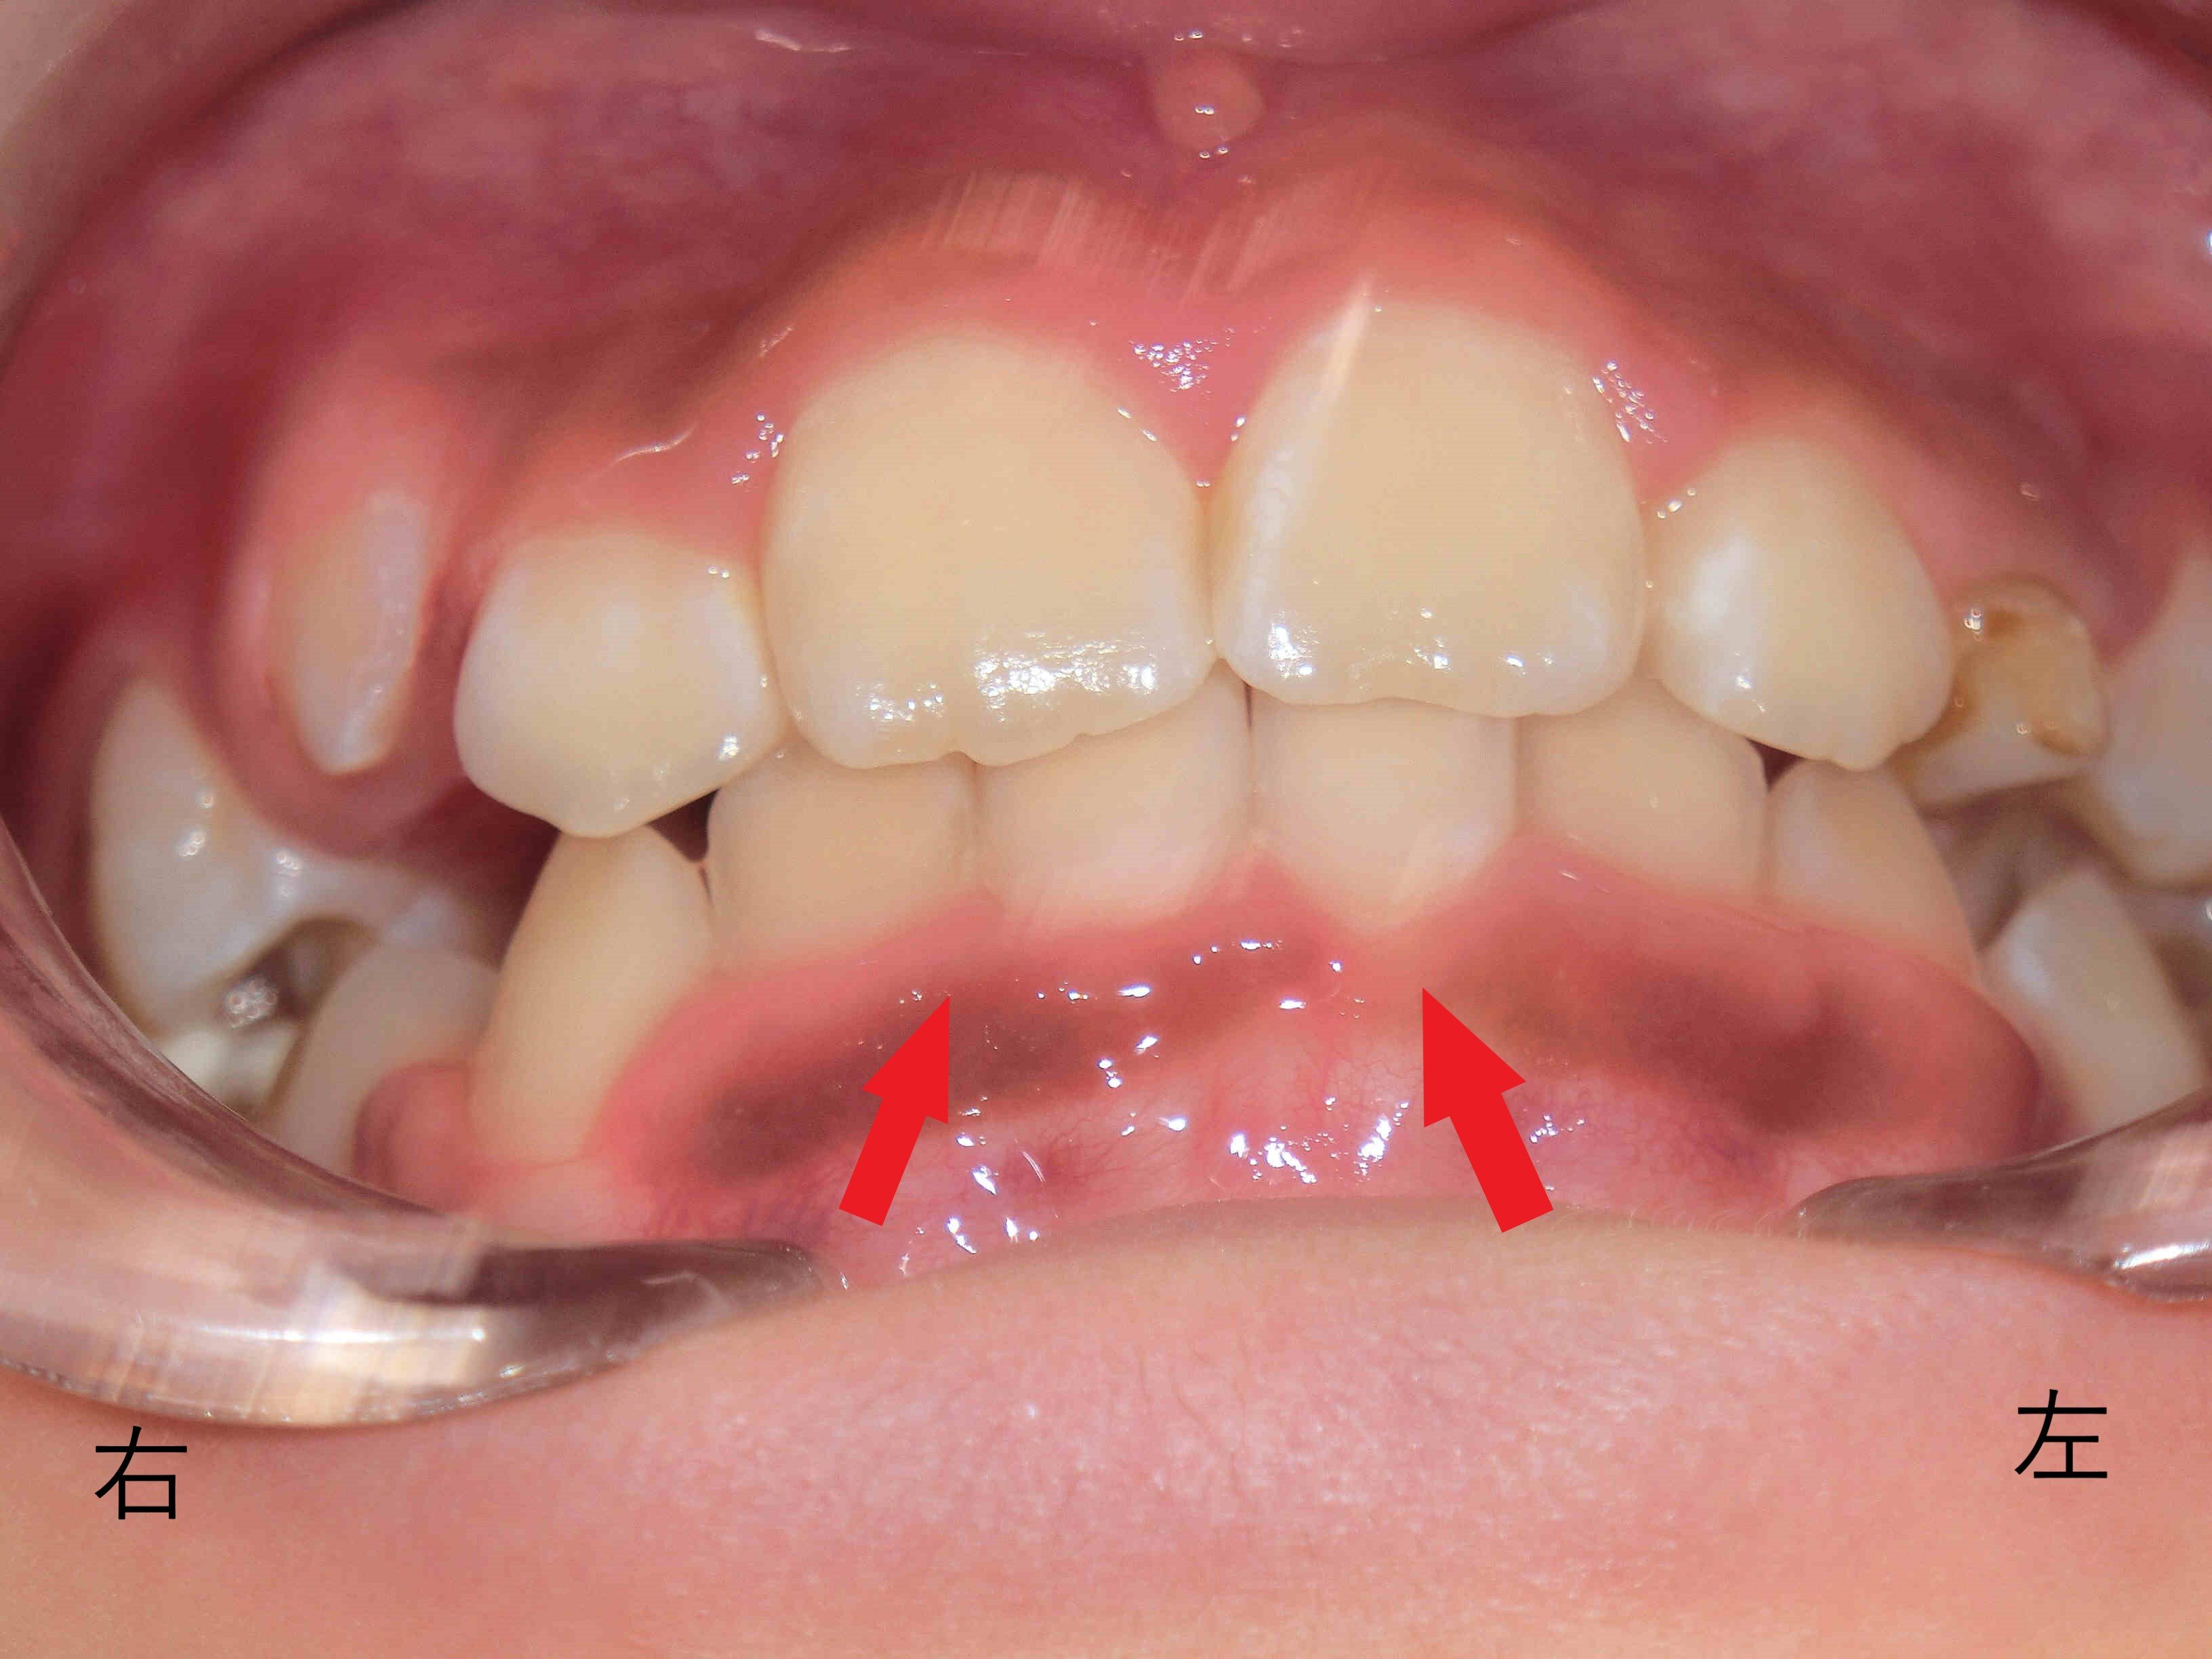

赤色矢印で示した下顎前歯が、上顎前歯(青色矢印)に隠れていた状態から、下顎の前方成長により前方から見えるようになってきています。

上顎の歯列は、V字型からU字型へと広がり、歯列の拡大が順調に進んでいます。下顎も同様に、叢生(凸凹の歯並び)が改善しつつあります。

噛み合わせが深かった状態から、下顎が前下方に成長することで浅くなり、より自然な咬合に近づいています。